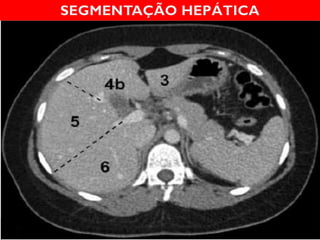

SEGMENTAÇÃO

HEPÁTICA

CLAUDE COUINAUD, 1957